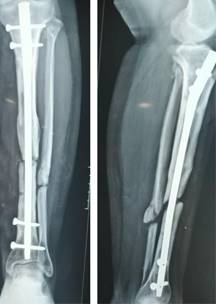

Después de nueve meses se observa no unión de espectro atrófico en tibia y peroné izquierdos (Figura 1) por lo que se decide su internamiento para realización de técnica de Masquelet, se informa a la paciente acerca del pronóstico y posibles múltiples procedimientos.

Figura 1: Radiografía a los nueve meses posteriores a la primera cirugía, con colocación de calvo centro medular, sin datos de consolidación.